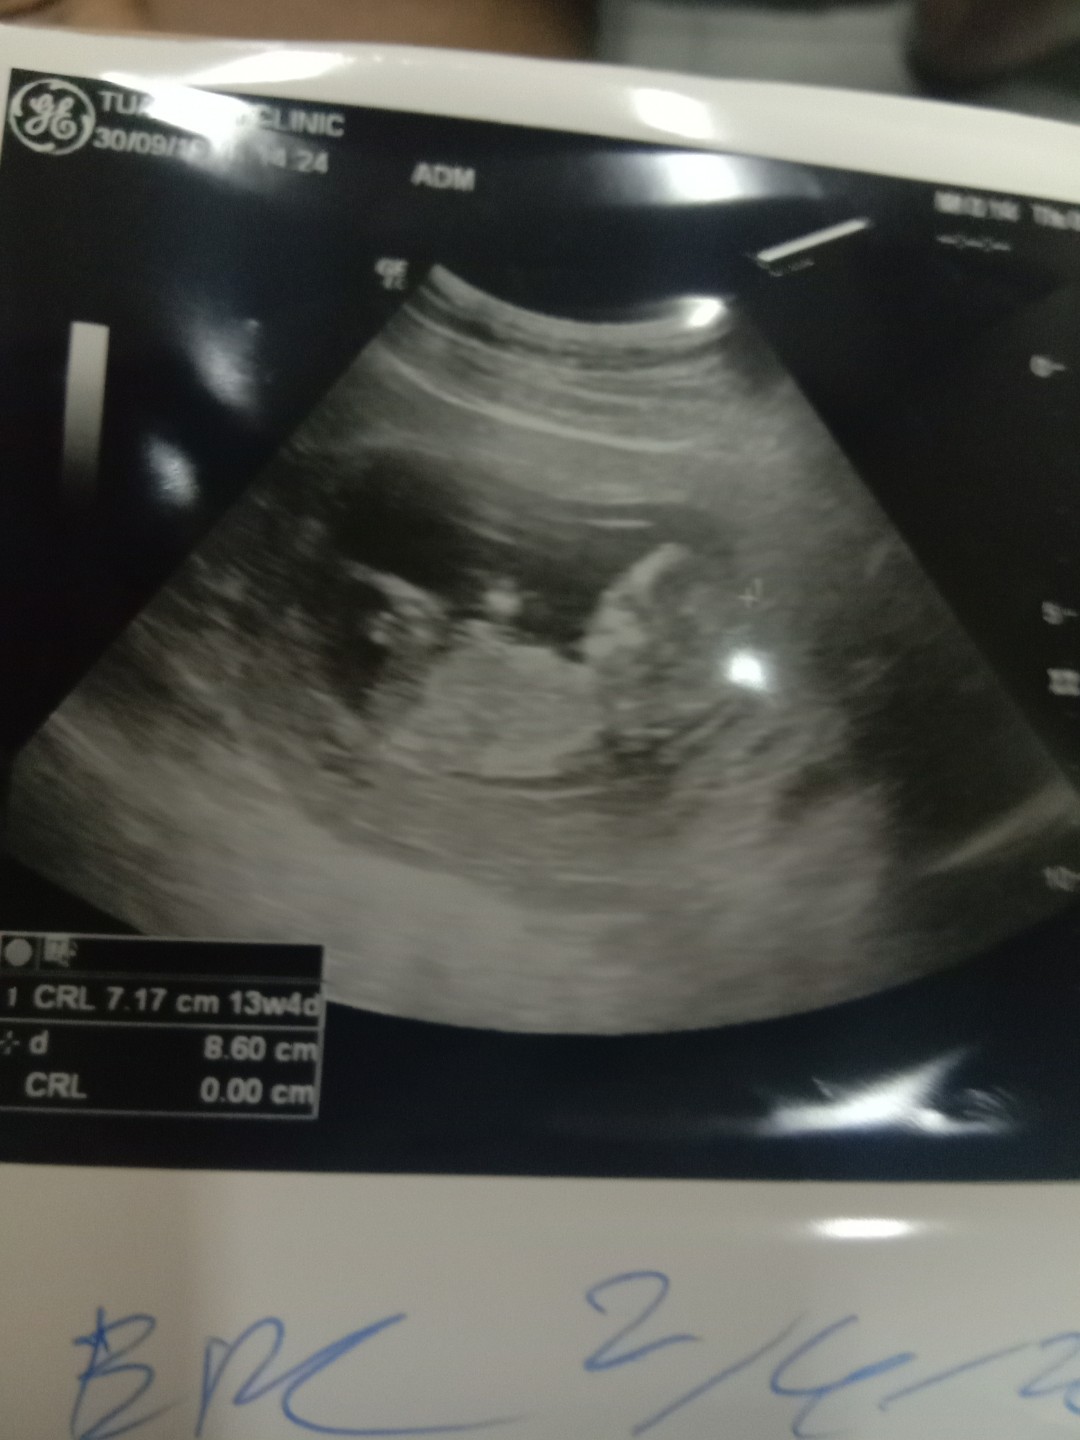

ขอดูใบซาวด์แม่เพศ ชาย หญิง หน่อยค่ะ

ลูกสาว จ้า

เพศหญิงค่ะ

สาวน้อยค่ะ

ลูกสาวค่ะ